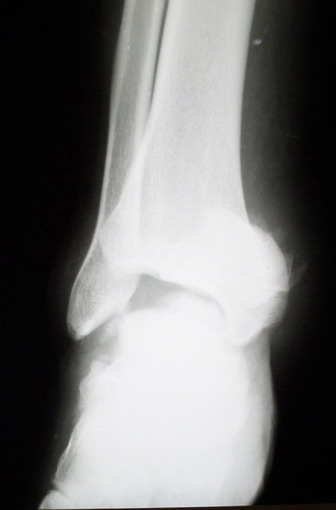

Ваша дискуссия заставила перелистать свои наблюдения.

Среди повреждений таранной кости (Hawkins III-IV) с одновременной травмой лодыжек встретилось следующее (см. вложение). Пациент упал в колодец на глубину 10 метров (Х.2002 г.), госпитализирован с диагнозом: з/перелом шейки правой таранной кости (Hawkins IV) с переломовывихом тела назад и кнутри, закрытый перелом внутренней лодыжки и переднего края большеберцовой кости. Оперирован в первые 12 часов после травмы, выполнена открытая репозиция таранной кости, внутренним и передне-внутренними доступами, остеосинтез переломов шейки и тела губчатыми винтами, для реваскуляризации тела таранной кости первичный компрессионный над- и подтаранный артродез. Синтез внутренней лодыжки губчатым винтом. Удаление винтов через 1 год,2 мес. Получен анкилоз указанных суставов с сохранением длины конечности, полная реваскуляризация таранной кости, о чем говорит сращение ее переломов, отсутствие отеков и

цианоза стопы и голени. Компенсаторная подвижность переднего и среднего отделов стопы около 15-20 градусов за счет поперечного (Шопара) сустава стопы. Считаю оправданной подобную тактику, не смотря на угрожаемый прогноз (100% асептический некроз) по классифицкации Hawkins.